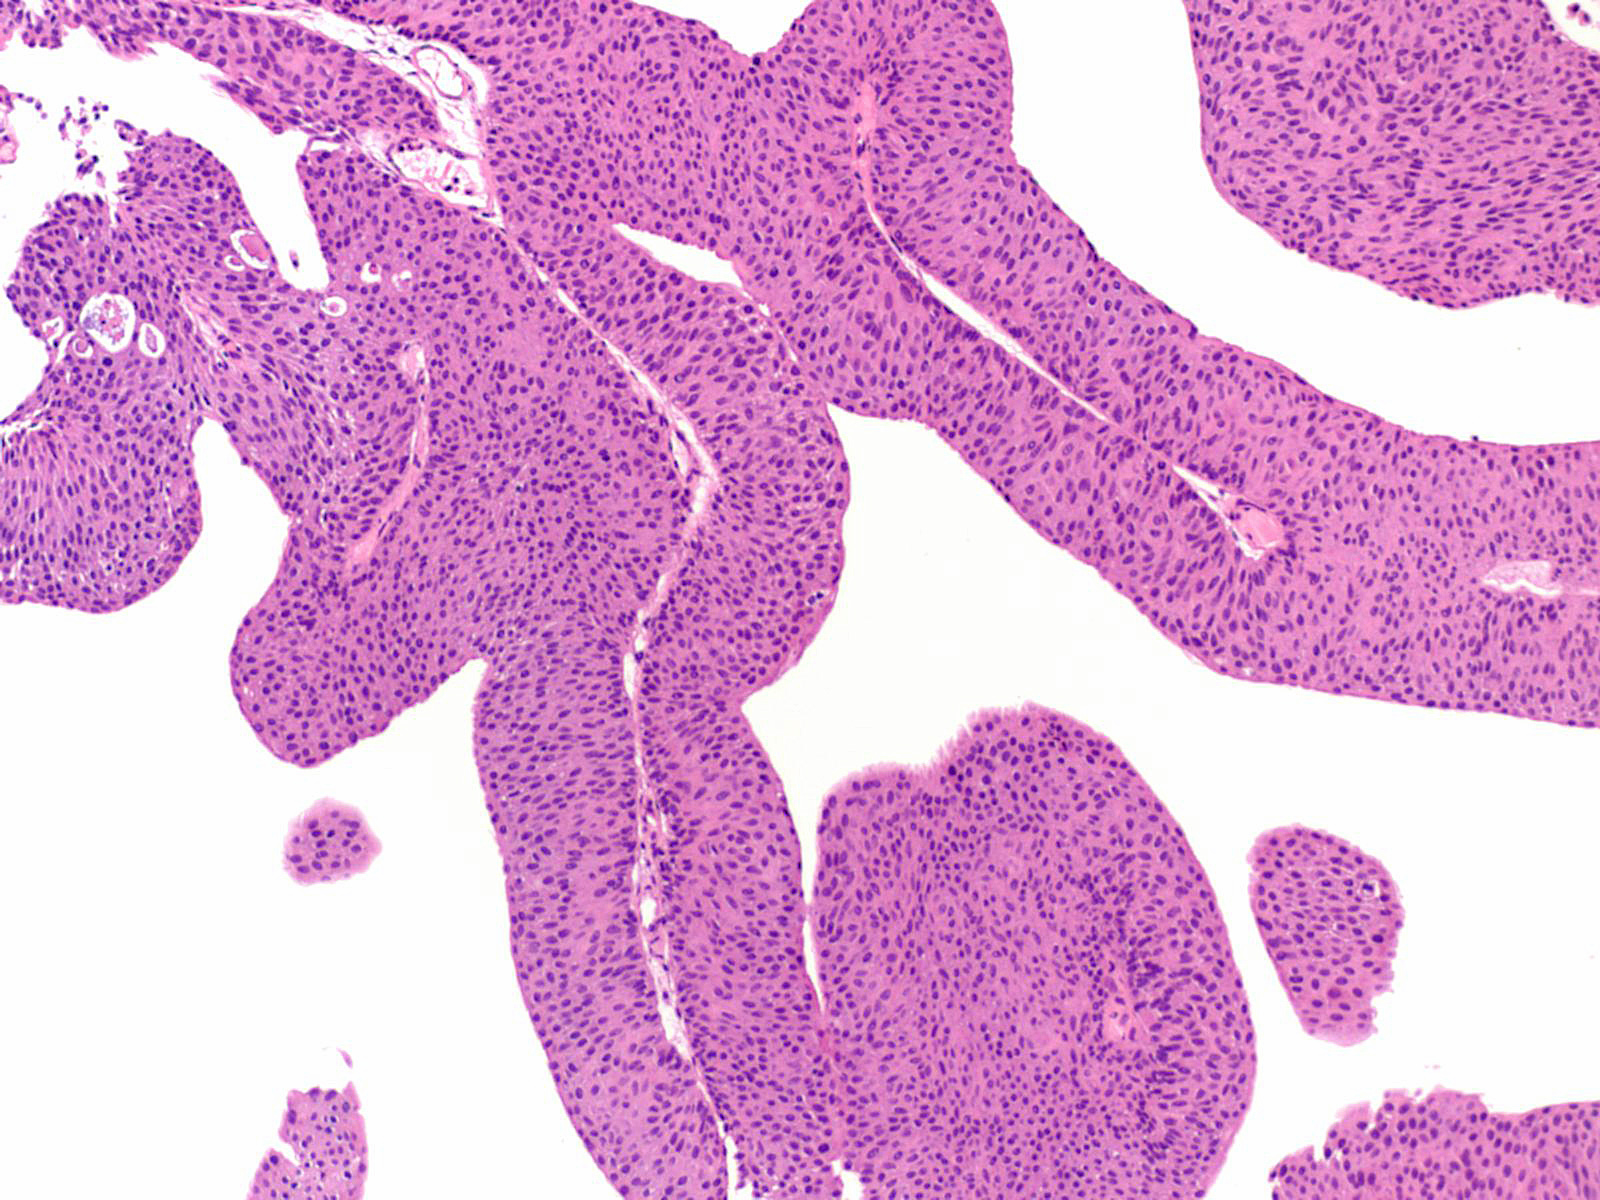

Consensus grade: Low-grade papillary urothelial carcinoma (LG-PUC)

Lesion shows moderate variation in nuclear size, shape and chromatin. Scattered nuclei are significantly enlarged and hyperchromatic relative to other nuclei. Lesion still maintains an overall orderly appearance.